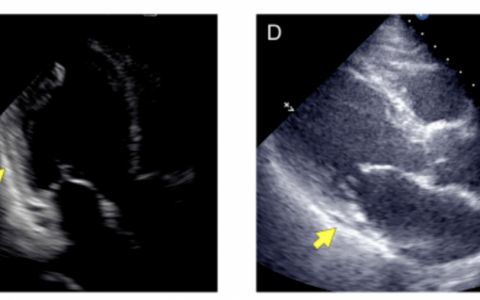

A 50-year-old woman presented to the emergency department with a 10-day history of a throbbing headache that had suddenly started after she had felt a “pop” in her back. The headache worsened with upright positioning and improved with lying flat. Physical examination, including fundoscopy, was normal. Magnetic resonance imaging of the brain showed diffuse pachymeningeal enhancement (arrow; upper left image, axial view, T1 sequence with contrast). It also showed protrusion of the cerebellar tonsils (arrow) into the foramen magnum, flattening of the pons with effacement of the prepontine cistern (arrowhead), and enlargement of the pituitary gland owing to increased blood flow (asterisk; right image, T1 sequence without contrast). Which of the following is the most likely diagnosis?

一位50岁女性因突发搏动性头痛10天就诊急诊科,其头痛始于背部突然”啪”的一声响后。该头痛在直立位时加重,平卧时缓解。体格检查(包括眼底镜检查)未见异常。脑部磁共振成像显示:弥漫性硬脑膜强化(箭头所示;左上图,轴位T1增强序列);小脑扁桃体疝入枕骨大孔(箭头);脑桥受压变平伴桥前池消失(箭头所示);垂体因血流增加而增大(星号;右图,T1平扫序列)。以下哪项是最可能的诊断?

磁共振成像(MRI)显示硬脑膜强化、小脑扁桃体异位、桥前池消失以及垂体充血——这些表现均符合自发性颅内低压的特征。自发性颅内低压是一种体位性头痛,由非医源性脑脊液(CSF)漏导致脑组织下沉引起。本例中,CT脊髓造影显示在T12-L1椎间隙腹侧存在硬膜外漏(箭头所示,左下图),病因是该节段的骨赘(骨刺)。经硬膜外血贴术治疗后,患者头痛症状完全缓解。